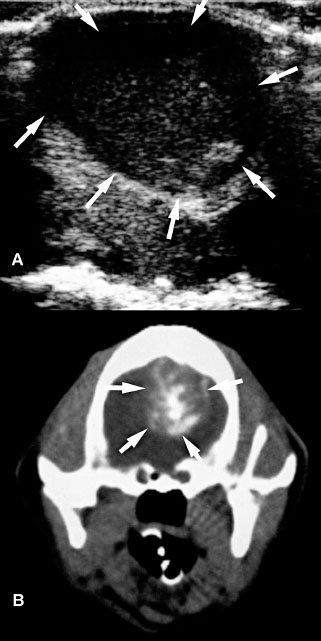

In most animals with brain neoplasia, MRI or computed tomography is used to make the initial diagnosis because the thick bone of the cranium precludes diagnosis with ultrasonography. Ultrasonography is more likely to be used either intraoperatively or postoperatively, although a window might provided by a persistent fontanel or by bone lysis associated with a neoplasm (Figure 1.13).

In rare instances, a brain abscess or granulomatous mass might occur in either a very young animal or an older animal with a persistent fontanel or other cranial defect (Klopp et al. 2000). Abscessation can appear as a cavitary and hypoechoic lesion containing swirling cellular material compressing the surrounding brain parenchyma (Figure 1.14).

In case of organized granuloma, a well-marginated hyperechoic lesion can be detected. Thus, a granulomatous mass should be considered as a differential diagnosis for neoplasia when a hyperechoic mass is seen on ultrasonography (Figure 1.15).

Figure 1.13. Astrocytoma in the cerebellum of an 8-year-old terrier. A: Magnetic resonance image shows a hyperintense mass (M) in the cerebellum. A craniotomy was done to enable an intraoperative ultrasound-guided biopsy of the mass. B: Transverse (trans) sonogram showing the hyperechoic mass (between the cursors) in the cerebellum. C: Parasagittal (long) sonogram showing the cerebellar mass. Images courtesy of D. Penninck and S. Hecht.

Figure 1.14. Abscess in the cerebrum of a kitten. The kitten had ventrolateral strabismus and soft-tissue swelling on its head. An abscess was diagnosed and drained via a palpable fontanel. A: Transverse ultrasonographic plane showing a large pocket of cellular fluid within the cerebrum (arrows). B: Transverse postcontrast computed tomography, on which a large, heterogeneous, contrast-enhancing mass lesion is observed (arrows).

Figure 1.15. Granulomatous meningoencephalitis in a 5-year-old Yorkshire terrier. A mass was identified in the brain stem and subsequently biopsied. The mass could be seen with ultrasonography performed at the foramen magnum although ventriculomegaly was not apparent from that location. A: Sagittal T1-weighted magnetic resonance image after intravenous administration of gadolinium showing a hyperintense lesion in the rostral brain stem (arrows). B: Transverse T2-weighted magnetic resonance image showing a hyperintense lesion in the brain stem to the right of the midline (arrows). The lateral and third ventricles are dilated. C: Sagittal sonographic image obtained through the foramen magnum. Cursors have been placed to measure the mass (arrows). D: Transverse sonographic image obtained through the foramen magnum. In the brain stem is a hyperechoic mass (arrows) just ventral to the cerebellar vermis (V).